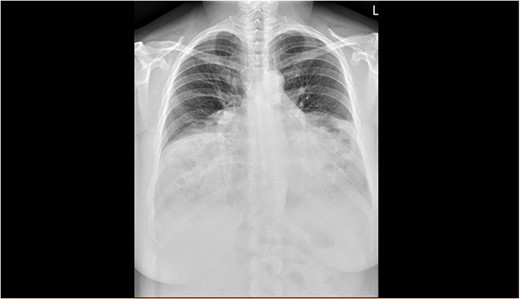

The spirometry results from her General Practitioner showed a restrictive pattern with FVC of 2.08L (55% predicted), FEV1 of 1.62L (54% predicted) and FEV1/FVC ratio of 0.78 (96% predicted). Her chest X-ray demonstrated a large hiatus or congenital hernia (Fig. 1). Subsequent computed tomography (CT) of the chest, abdomen and pelvis showed a large 88 × 48-mm defect of the anterior diaphragm consistent with MH. Hernial contents extended to the superior mediastinum and were primarily large bowel and omentum, with no intestinal obstruction (Figs 2–4).

Arterial contrast CT of the chest. Sagittal slice in the midline of the body. The diaphragmatic defect is clearly seen anteriorly, and the abdominal contents are seen extending to the superior mediastinum.